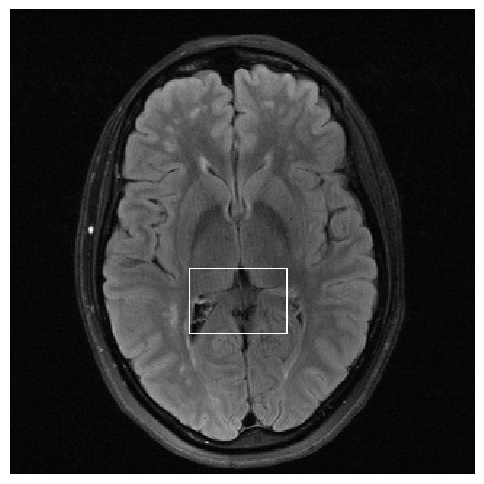

Figure 3: Reconstructions results. Rows 1 and 3: Examples of comparing the ground truth (GT) fully sampled image to the reconstructed images obtained by the three models (1-3), NPB-REC, baseline, E2E-VarNet trained with Dropout, and the NPB-REC std. map at accelerations R=4𝑅4R=4italic_R = 4, R=8𝑅8R=8italic_R = 8, respectively. Rows 2 and 4: The corresponding annotated ROIS of Nonspecific white matter lesions.

Fig. 3 presents examples of reconstruction results obtained by (1) our NPB-REC approach, (2) the baseline, and (3) Monte Carlo Dropout, for equispaced masks with two different acceleration rates R=4𝑅4R=4italic_R = 4 and R=8𝑅8R=8italic_R = 8. The reconstructed images predicted by the three models are smoother than the reference image. This is due to the fact that all the models were trained with SSIM loss, which tends to produce overly smooth reconstructions while preserving the diagnostic content and the anatomical features Sriram et al. (2020a). These images can be enhanced by dithering the image by adding a small amount of random Gaussian noise to produce a more textured reconstruction, as proposed in Sriram et al. (2020b).

Table 1 presents the mean PSNR and SSIM metrics, calculated over the whole inference set, for the three models. Our NPB-REC approach achieved significant improvements over the other methods in terms of PSNR and SSIM (Wilcoxon signed-rank test, pmuch-less-than\ll1e-4, except for SSIM values in line W, R=4𝑅4R=4italic_R = 4 where they are roughly the same for NPB-REC and Baseline). The improvement in the reconstruction performance can be noted both quantitatively from the metrics, especially for masks with acceleration rate R=8𝑅8R=8italic_R = 8, and qualitatively via the images of annotations, where our results show less smoothness than those obtained by Dropout.